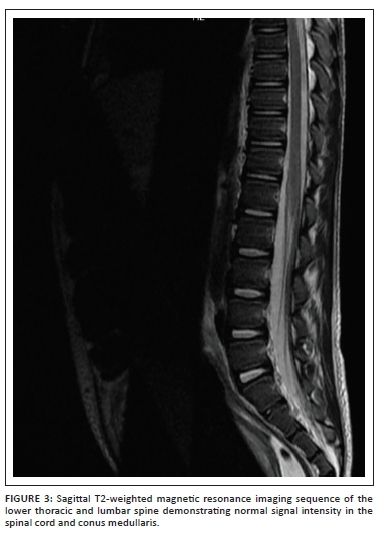

The voiding cysto-urethrogram was normal with no features of vesicoureteral reflux or posterior urethral valves. Magnetic resonance imaging (MRI) of the thoracic and lumbar spine (Figure 3) was conducted to exclude a neurological aetiology. This demonstrated no features of spinal dysraphism or spinal cord abnormality; however, bilateral hydronephrosis was evident as documented on ultrasound. Incidentally, the MRI also demonstrated a homogenous cystic lesion within the prostate gland (Figure 4) with mass effect on the bladder base. Only limited sequences through the prostate were obtained and contrast was not administered. Given the background of failure to respond to medical treatment and the progressive symptoms, a PA was considered as the likely aetiology for the obstructive uropathy.

Magnetic resonance imaging defines the cross-sectional anatomy of the prostate with greater tissue differentiation compared to computed tomography (CT). The prostate shows homogenous signal intensity on MRI imaging that is isointense to muscle on T1-weighted images and iso- to hyper-intense to muscle on T2-weighted images before puberty. After puberty, the signal characteristics resemble those of the adult prostate.9 A prostate abscess appears hypointense on T1-weighted MRI and hyper-intense on T2-weighted images.1